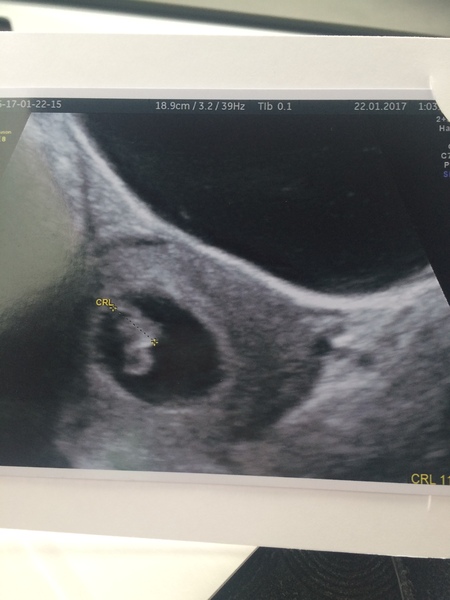

Amz26 · 22/01/2017 13:34

everything went well today at the scan! They said there was a strong heartbeat and everything looked good... It was so emotional 🙈 I thought I was 7weeks 2days but she thought I was 7+4 days so I was really close anyway xx

Dixiechick1991 · 22/01/2017 14:19

Hello. WEnt for another reassurance scan today after being told last week that I was only 5-6 weeks, I'm now 7+3 with baby measuring 11.5mm and a tilted uterus.

Got to see a tiny little blob with a heartbeat & new due date of 7th September

I've gone from 25th August to 15th September to 7th September.